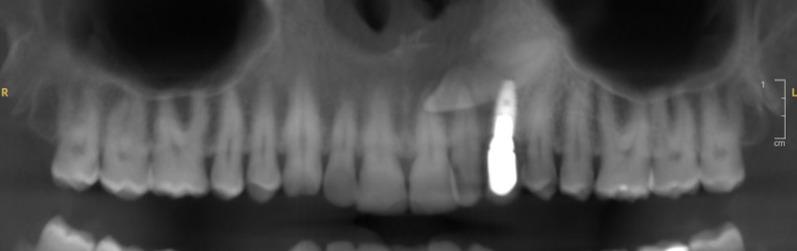

A 42-year-old man presented with persistent swelling and pain in the maxillary region associated with a transcanine implant placed one year ago by his dental practitioner. Imaging assessment showed the implant's apex inserted into the impacted canine which presented a crown and root resorption and was associated to a radiolucency around. In order to preserve implant and reduce morbidity related to a full extraction of the tooth, a coronectomy was performed allowing inflammatory surrounding tissues curettage.

This case shows an infectious complication of a transcanine implant and demonstrates an approach for managing these complications while preserving this implant. The coronectomy is a less invasive technique that reduces potential surgical complications and supports healing. A 2-year follow-up revealed complete bone reossification reinforcing the effectiveness of this method in similar clinical scenarios.

一名42岁男性因上颌区域持续肿胀和疼痛前来就诊,其一年前由牙医植入了一枚经尖牙种植体。影像学评估显示种植体根尖插入阻生尖牙,该尖牙出现冠部和根部吸收,并伴有周围的透射区。为了保留种植体并降低因完全拔除牙齿而导致的发病率,进行了冠切除术,以便刮除周围的炎性组织。

本病例显示了经尖牙种植体的感染并发症,并展示了在保留该种植体的同时处理这些并发症的方法。冠切除术是一种侵入性较小的技术,可减少潜在的手术并发症并促进愈合。两年的随访显示完全骨再矿化,加强了该方法在类似临床情况下的有效性。